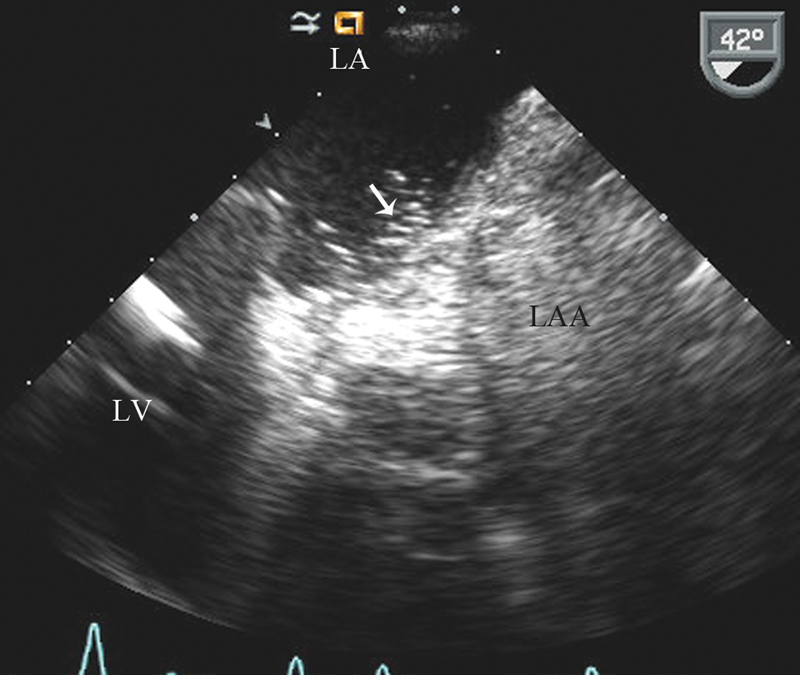

فحوصات تشخيصية لبعض امراض القلب والشرايين التاجية